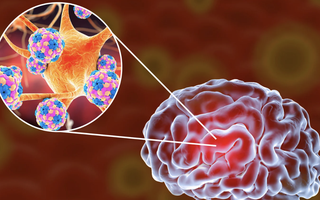

Ai bị cúm nên chú ý điều này

(NLĐO) - Hiện nay, thời tiết giao mùa tạo điều kiện thuận lợi cho virus cúm phát triển và lây lan nhanh chóng.